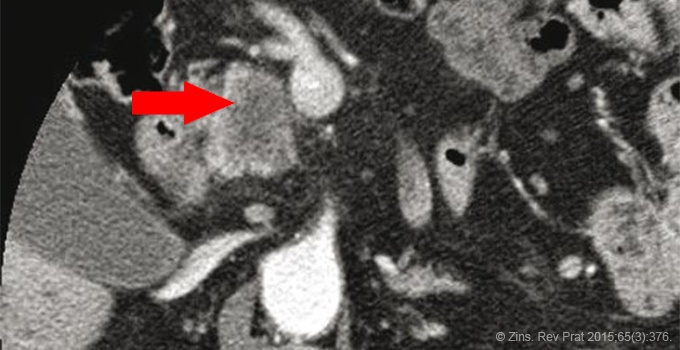

La tomodensitométrie (TDM) permet de visualiser la plupart des lésions tumorales et de rechercher des contreindications chirurgicales (métastases, adénopathies, envahissement vasculaire). Mais dans 5 à 15 % des cas, la lésion est isodense au pancréas et donc n’est pas visible directement. L’IRM a pour principal avantage son excellente résolution en contraste et donc sa capacité à mieux identifier la lésion primitive.